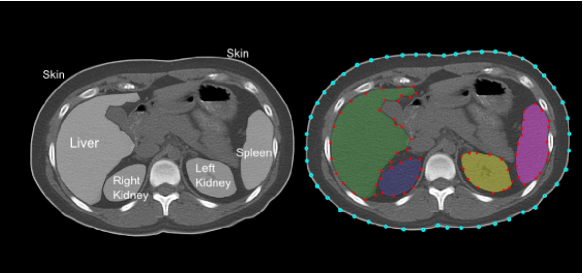

Figure 1 shows annotated landmarks for five different objects (skin, liver, right kidney, left kidney, spleen) in a CT slice of the abdominal region. Note that different number of landmarks are used for different objects considering their size.

![]() |

Figure 2 shows multi-object 3D ASMs for abdominal organs. Note that skins are also considered in the s to restrict the search space. Note also that mean shapes of the objects do not have any overlapped region with other mean shapes of the objects. Because, in training part, we select the objects such that , implying that there is no overlaps across the objects. This fact leads to , as each mean shape is created independently and alignment of the shapes of objects does not affect the distribution of objects in the mean shape due to the nature of the 7-parameter affine transformation : . Objects are not aligned individually, hence, their spatial relations before and after alignment does not change.

|